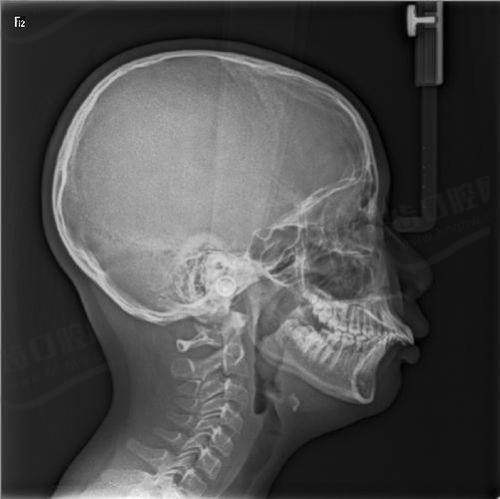

2.设备齐全:必备CBCT和3D打印技术,CBCT可精细测量颌骨角度,3D打印矫治器贴合度更高,减少复诊次数。